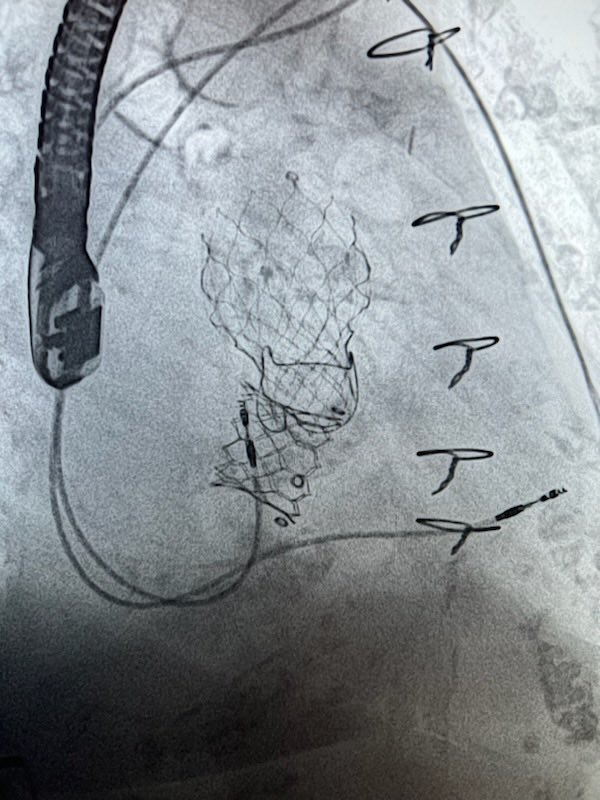

CoreValve 29mm implanted October 2011…still going strong after 12 years…mean gradient 6mmhg and trace PVL in June 2023… The future is promising Atlantic Health Medtronic Edwards TAVR TAVR Bot David J. Cohen, MD, MSc Linda Gillam MD, MPH, MACC, FASE, FAHA, FESC Jordan Safirstein MD Dr. Gilbert Tang Michael Katz Philippe Genereux